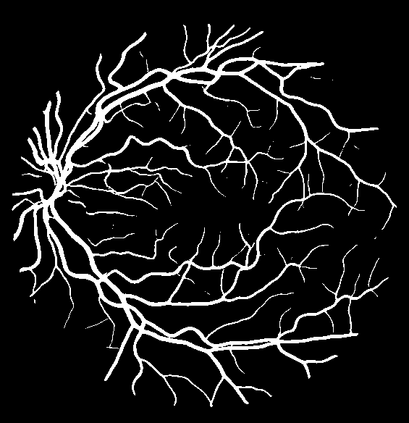

Blood vessel segmentation is crucial for many diagnostic and research applications. In recent years, CNN-based models have leaded to breakthroughs in the task of segmentation, however, such methods usually lose high-frequency information like object boundaries and subtle structures, which are vital to vessel segmentation. To tackle this issue, we propose Boundary Enhancement and Feature Denoising (BEFD) module to facilitate the network ability of extracting boundary information in semantic segmentation, which can be integrated into arbitrary encoder-decoder architecture in an end-to-end way. By introducing Sobel edge detector, the network is able to acquire additional edge prior, thus enhancing boundary in an unsupervised manner for medical image segmentation. In addition, we also utilize a denoising block to reduce the noise hidden in the low-level features. Experimental results on retinal vessel dataset and angiocarpy dataset demonstrate the superior performance of the new BEFD module.